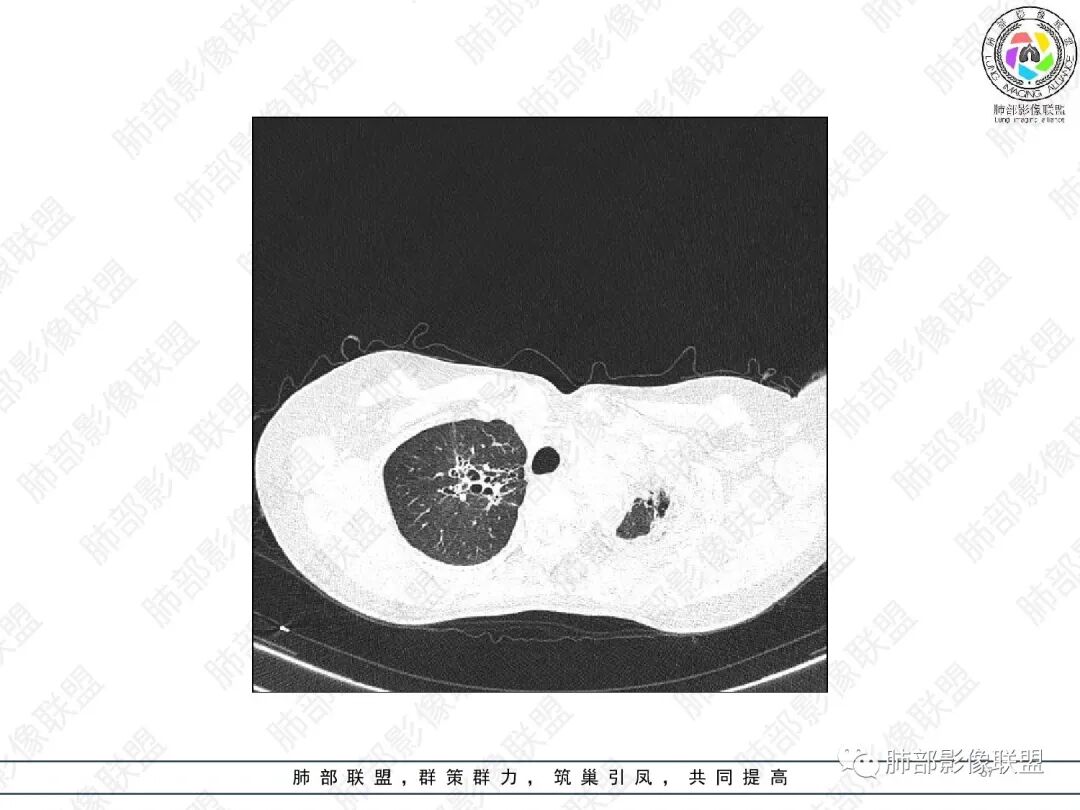

1.中年女性,主因“咳嗽、咳痰半年余”入院,既往史:8年前因左肺病在外院变行左肺叶切除术,诉术后抗结核治疗1年,具体病理等不详。实验室IGE显著增高。

2.胸部CT:右肺上叶及中叶不规则块状影,沿支气管走行方向指套样影,支气阻塞湖嵌塞,腔内可见高密度影。灶周可见磨玻璃,外围见结节影及树芽征。左肺体积缩小,见不规则条索影、胸膜增厚,纵隔牵拉左移。

3.综合分析:结合患者病史及胸部CT主要鉴别ABPA(右肺上叶不规则块影,指套样顺延支气管方向,抗结核治疗1年,肺部病灶仍明显)及继发性肺结核TB(右肺上叶不规则肿块,其可见高密影,边缘模糊,周围卫星灶、树芽征,沿支气管爬行)。

完善气管镜及病理、检验结果(IgE显著增高)等支持ABPA诊断。且给予激素及伊曲康唑治疗后复查胸部CT提示病灶较前吸收,所以诊断明确。